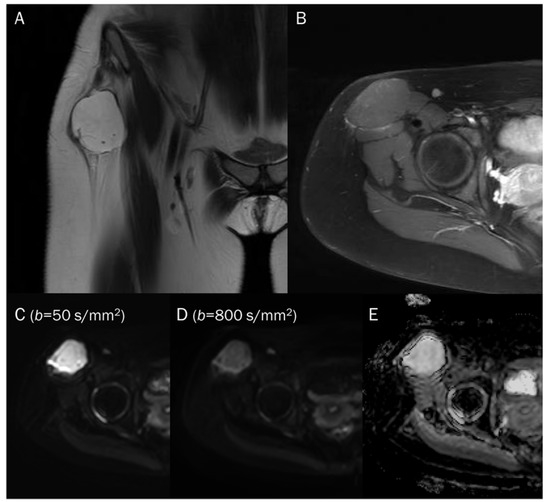

7.1. Cyst

| Benign cyst | T2 shine-through | Free water |